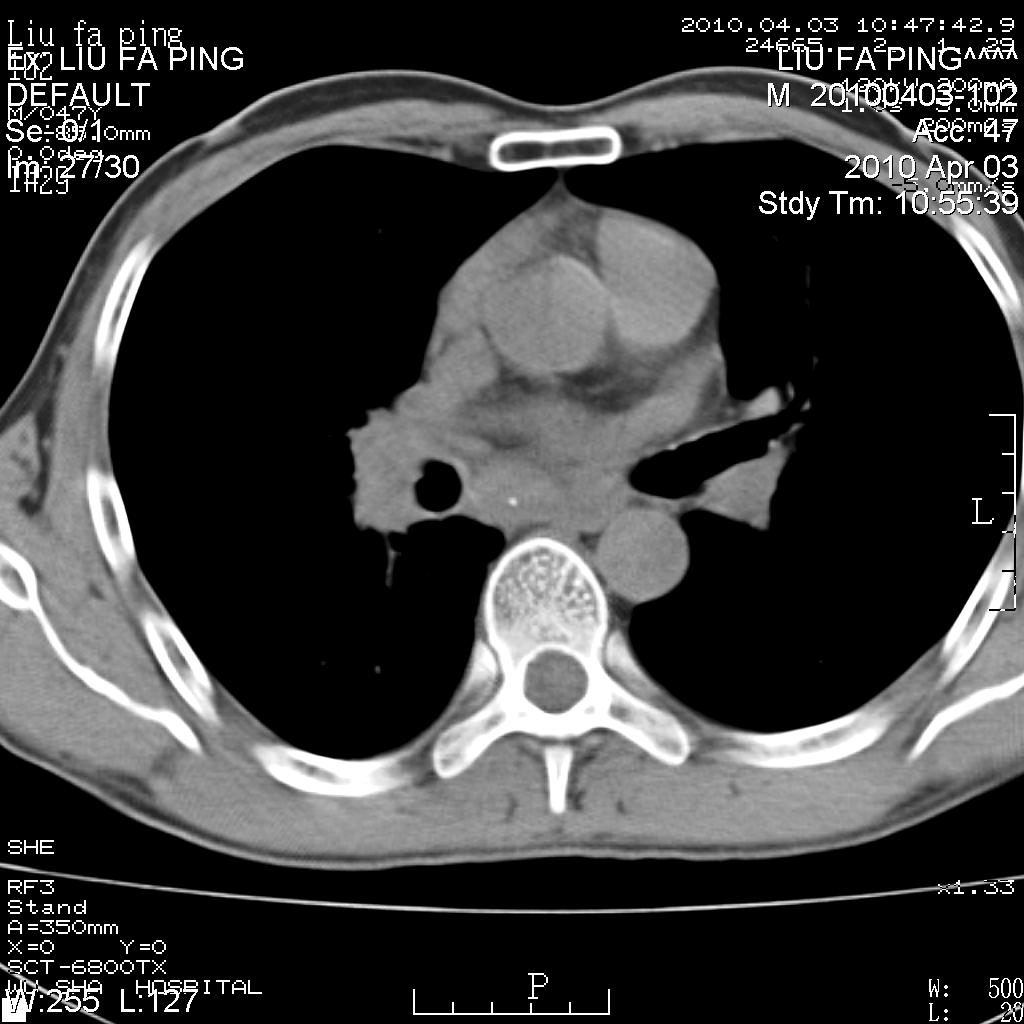

标题: CT25875:咳嗽数天。

平时身体健康,无不适

男性47岁,考虑中心性肺癌合并阻塞性肺炎,纵膈淋巴结肿大。肺内及纵膈淋巴结钙化。

建议支气管镜检

支持右侧中央型肺癌伴右肺上叶阻塞性炎症、纵膈淋巴结转移,建议纤支镜检查!

男性47岁,考虑中心性肺癌合并阻塞性肺炎,纵隔淋巴结肿大。肺内及纵隔淋巴结钙化。

考虑右肺中央型肺癌并阻塞性肺炎,右肺门及纵隔淋巴结转移;建议必要时行纤支镜检查进一步明确诊断。